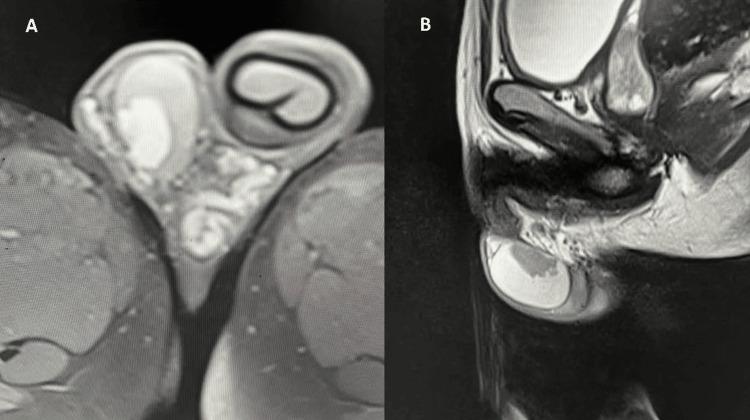

Testicular adrenal rest tumors (TARTs) are benign, adrenal-like hyperplastic lesions that occur ectopically within the testes. They are most commonly observed in male patients with congenital adrenal hyperplasia (CAH), especially in those with inadequate glucocorticoid therapy and consequent poor hormonal control. Chronic elevation of adrenocorticotropic hormone (ACTH), driven by insufficient cortisol replacement, stimulates the growth of adrenal rest cells within the testes, leading to tumor formation. Although TARTs are non-malignant, their clinical significance lies in the potential for testicular dysfunction, structural abnormalities, and infertility if left undiagnosed or untreated. Early detection through imaging is essential to guide clinical management and preserve reproductive function. We report the case of an 11-year-9-month-old boy diagnosed with the salt-wasting form of CAH secondary to 21-hydroxylase deficiency. Due to long-standing poor compliance with glucocorticoid therapy, the patient developed bilateral TARTs as a result of chronic ACTH overstimulation. Magnetic resonance imaging (MRI) of the scrotum revealed multiple well-defined, bilateral testicular masses that appeared T2-hyperintense with mild post-contrast enhancement, features consistent with TARTs. This case emphasizes the pivotal role of MRI in the accurate diagnosis and longitudinal monitoring of TARTs in pediatric patients with CAH, particularly those with suboptimal hormonal control.